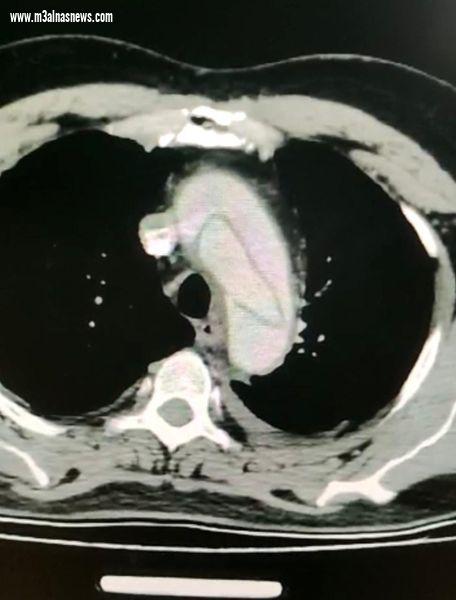

نجح قسم جراحة القلب والصدر بمستشفى أسيوط الجامعي في إجراء عملية جراحية لإصلاح انشطار بالشريان الأورطي لمريض يبلغ من العمر 46 عاما ، كان يعاني من آلام شديدة بمنطقة الصدر وأعلى الظهر ، حيث أجراها فريق طبي من العديد من التخصصات الطبية برئاسة الأستاذ الدكتور أحمد غنيم رئيس قسم جراحة القلب والصدر.

من جانبه قال الأستاذ الدكتور أحمد غنيم، أن جراحات انشطار الشريان الاورطي من العمليات المعقدة و التي تحتاج إلى سرعة في التشخيص و سرعة في التدخل الجراحي ، و مرضى هذا النوع من الأمراض في الغالب تتراوح أعمارهم فيما بين العقد الثالث و الربع من العمر .

واضاف الدكتور محمد فاروق مدرس جراحة القلب والصدر ، أن هذا النوع من العمليات يستلزم فريق جراحي كبير يضم عدة تخصصات كالجراحين و أطباء التخدير ، و تستغرق مدة هذه العمليات من ٦ الي ١٠ ساعات في بعض المجالات ، وبعد الإنتهاء من العملية ينتقل المريض إلى الرعاية المركزة لمتابعة الحالة إلى أن تستقر